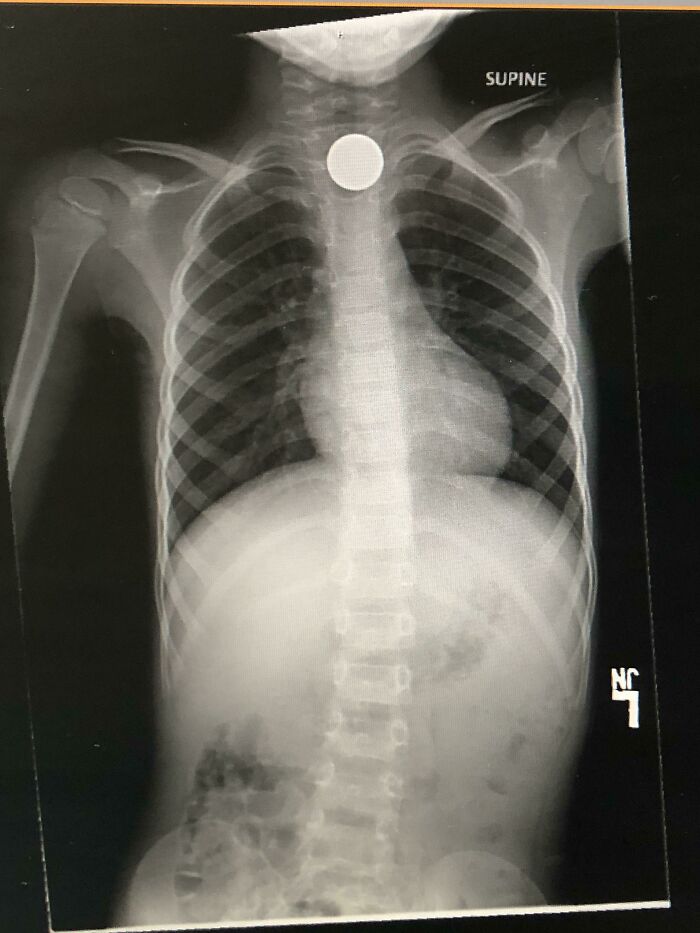

"Can’t Wait For 2020 To Be Over" They Said. They Obviously Never Met My Kid Who Decides To Swallow A Screw To "Transform" Into Optimus Prime

Just hours after our deductible reset to $0.